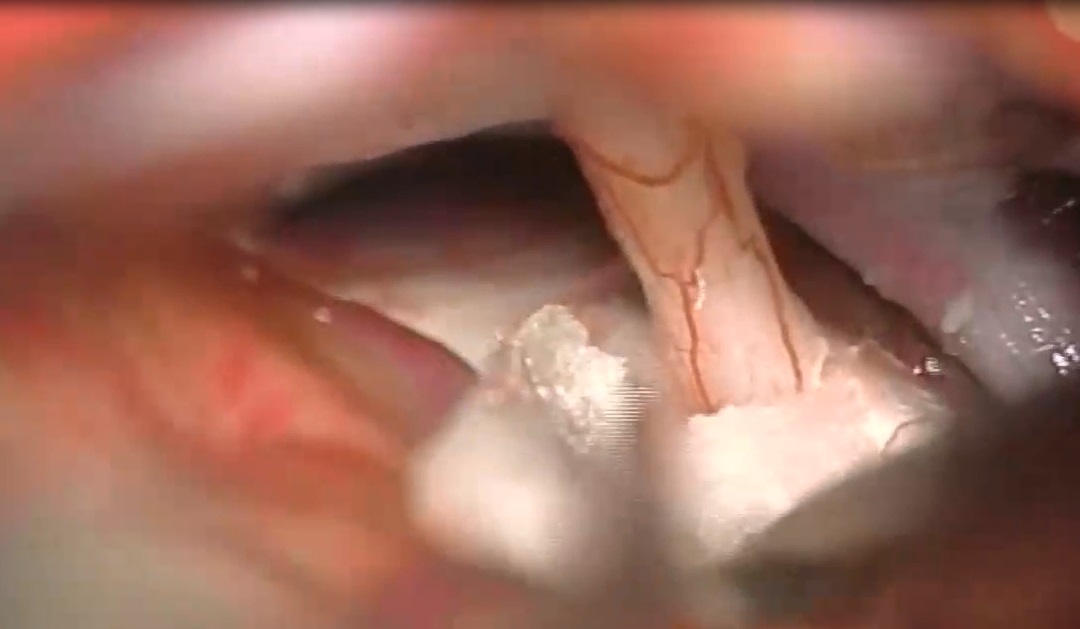

术中情况:患者视路、视交叉肿胀明显。通过翼点入路视角处理丘脑胶质瘤的情况。直接切开视交叉部位,然后打开中板,松解嗅神经,否则会因牵拉额叶造成嗅神经嗅丝断裂。三室完全被肿瘤充满,好消息是肿瘤和脑室壁有很好的界限。瘤脑界面清楚,肿瘤大部分清除,先做活检。做完活检,然后kusa进行肿瘤大部分减容,要分离的时候牵拉轻柔,不要把肿瘤夹得过碎,以方便大块切除。1.4mm 检查周围穿支保留及是否有肿瘤残留,仔细检查瘤仓的各个角落,以确保没有残留,肿瘤全切。

肿瘤充满三室

将肿瘤从脑室壁分离下来

使用cusa进行肿瘤大部分减容

将小的供血支烧灼、剪断

检查是否有肿瘤残余及血管保留情况,术中图片显示肿瘤全切除